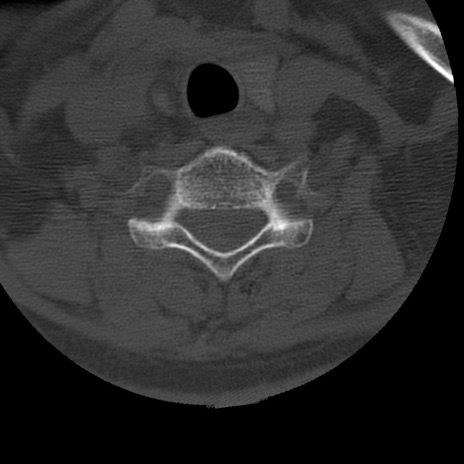

症例50 頚椎CT(横断像)

冠状断像